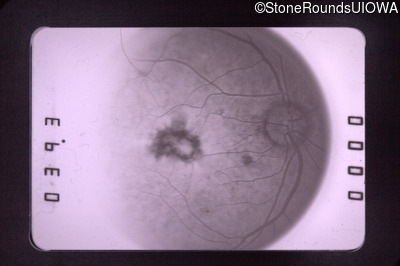

Visit at age: 59 years

Fundus Photography - Left - 20/40

Exemplar